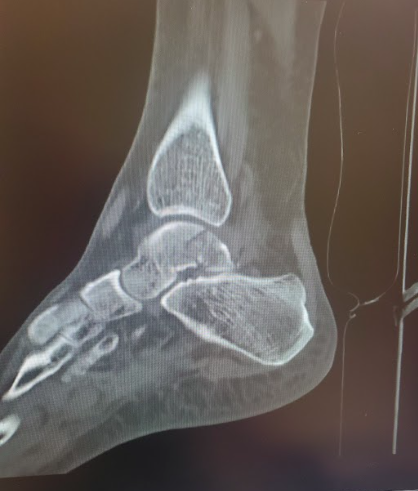

Talus Fracture

Pre-op CT images